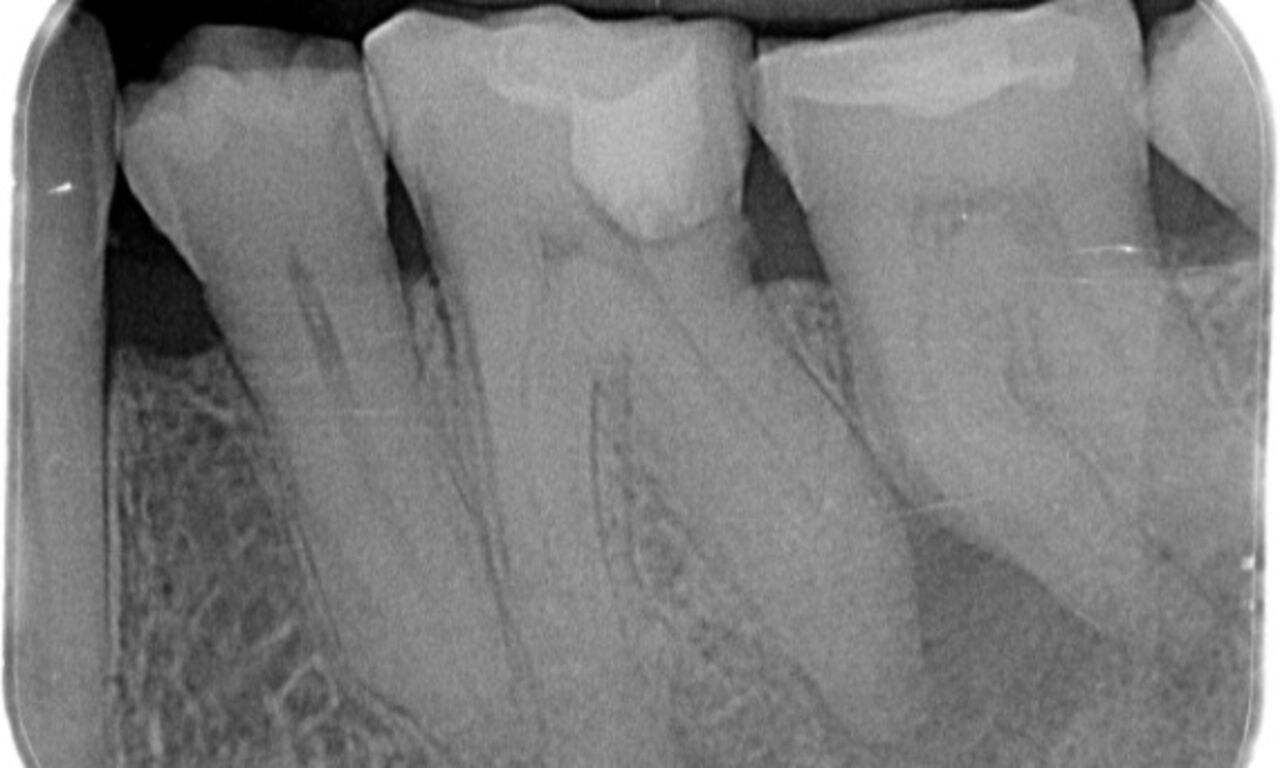

Before

Upon examination, there was a caries lesion related to the lower right first molar. Radiographic examination revealed proximity of the lesion to the pulp horn and combining it with the chief complaint, a final diagnosis of chronic irreversible pulpitis was concluded.